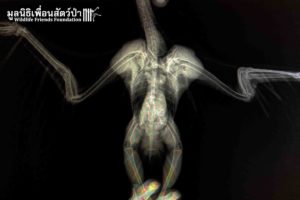

Meet WFFT’s newest resident ‘Rango’. Rango is a Brahminy kite (Haliastur indus) that arrived at WFFT a few days ago with deformed wings. His wings were broken in an accident when he was a chick, but luckily he was found and raised by some kind people.

At 2 years old Rango’s owners felt he needed a more suitable home and so they decided to bring him to us. He is now in quarantine adjusting to his new surroundings. We will ensure he is in good health before introducing him to other Brahminy kites housed at WFFT. Some may argue why keep a flightless bird alive, unless the animals welfare is severely compromised we will give him a chance at a happy life. We have another kite with only one wing that arrived earlier in the year; this kite now lives happily in a large aviary with his own species.